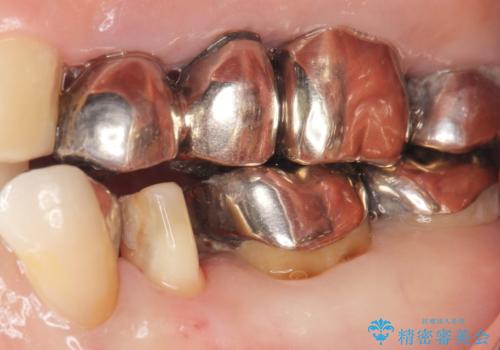

- 虫歯と歯並びを治したいとご希望された患者様です。

精査したところ、左下の小臼歯(左下5)の銀の詰め物の下に大きなう蝕を認めました。

またその手前の歯(左下4)は頬側転位していることを気にされておりました。